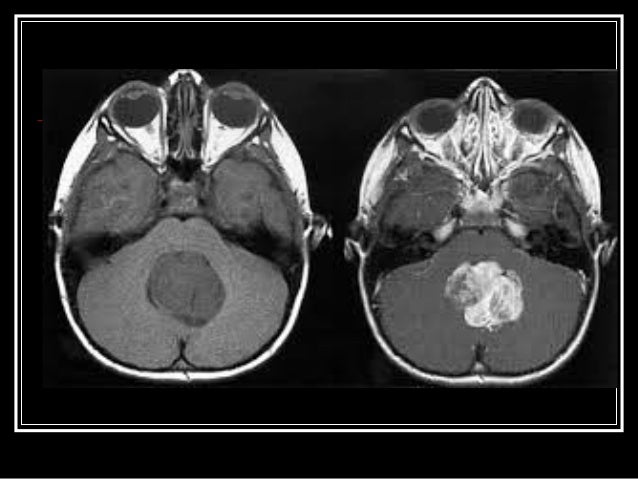

8. 8. Benign Tumors- not cancerous May grow larger but do not spread to other parts of the body.

9. 9. MALIGNANT Masses of cells that are cancerous. They may spread to other parts of the body.

10. 10. What is the difference between benign and malignant tumors?  They can often be removed, and, in most cases, they do not come back. Cells in benign tumors do not spread to other parts of the body. Malignant tumors are cancerous and are made up of cells that grow out of control. Cells in these tumors can invade nearby tissues and spread to other parts of the body.